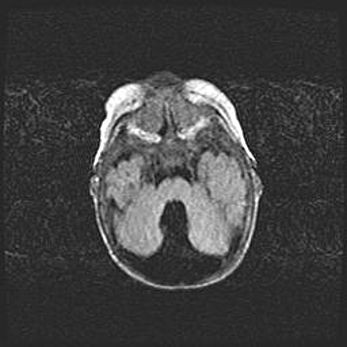

Подострая гематома правой гемисферы мозжечка.

Наружная гидроцефалия.

Возраст: 15 дней

Вес: 3100 г

Пол: женский

Окружность головы: 37 см

Срок гестации: 35-36 недель

При открытой наружной форме гидроцефалии у новорожденных расширяются и переполняются субарахноидные пространства.

Кровоизлияния в мозжечок имеют две клинико-анатомические формы: полушарные гематомы и кровоизлияния в червь.

К появлению этой патологии может привести: повреждения головного мозга, возникающие в результате асфиксии и гипоксии плода при беременности, или травмы во время родов. Редко гематома мозжечка может быть результатом первичной коагулопатии и сосудистой мальформации, диссеминированном внутрисосудистом свертывании, изоиммунной тромбоцитопении.